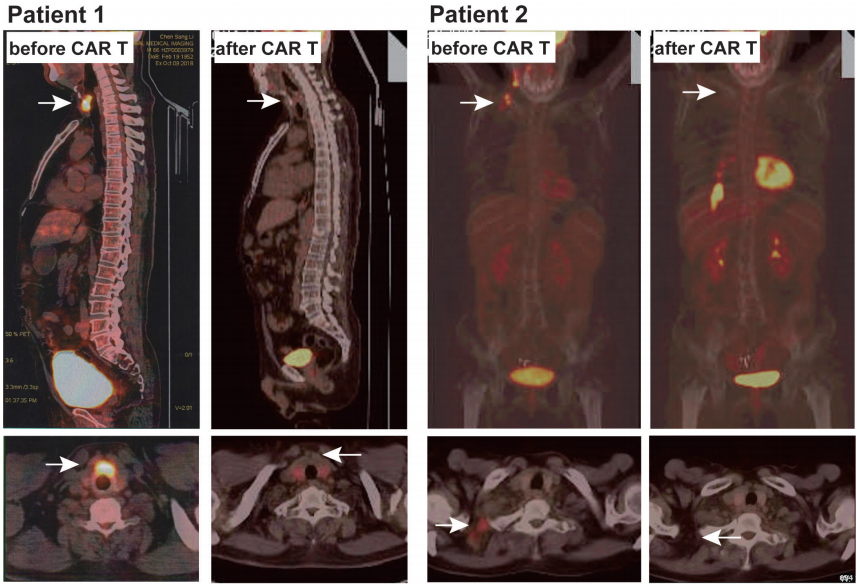

超声提示甲状腺结节为0.8*0.6 cm(图2),甲状腺超声提示甲状腺炎症,甲状腺功能T3、T4、TSH在正常范围内,抗甲状腺过氧化物酶抗体和甲状腺球蛋白抗体升高。考虑继发性桥本甲状腺炎。

图2. 两名患者CAR T治疗后的甲状腺超声图像